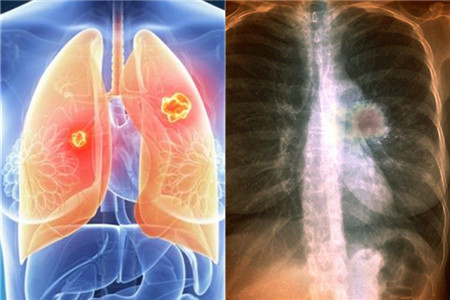

我们生活在当下时代,不得不说是幸运与不幸的结合。之所以幸运是因为经济快速发展,人们已经摆脱了基本的物质生活需求。不幸是因为环境遭到了破坏,长期生活在劣质环境中,难免会患上肺癌等各种病症。那么,怎样预防肺癌发生呢?